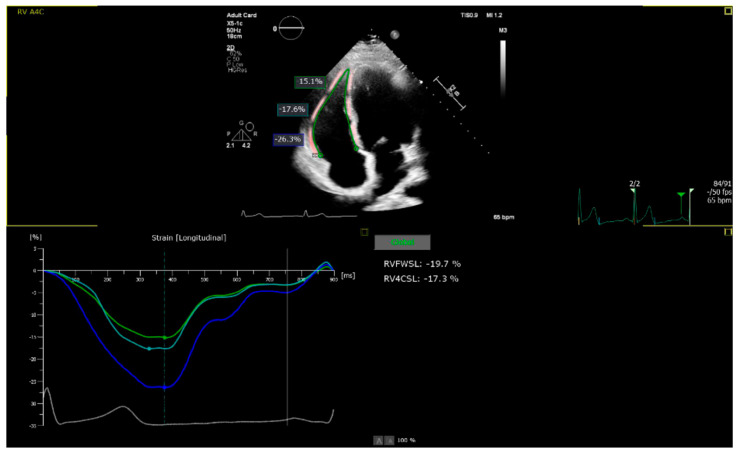

目的:本研究旨在探讨超重和肥胖青少年和青壮年个体右心室(RV)参数、功能和体成分之间的关系。我们假设身体成分异常与右心室功能障碍和心室亚临床变化有关。方法:该研究前瞻性地纳入了80名年轻人,其中55人超重或肥胖,25人体重正常。我们检查了两组间右心室超声心动图参数的差异及其与身体成分参数的关系。结果:超重或肥胖的青少年和青壮年右心室压力负荷更大,右心室直径更大。各组间RV大小和品系差异有统计学意义。在整个队列中,瘦体重与RV菌株呈正相关,脂肪质量和血清总蛋白与RV菌株负相关(p < 0.01或更低)。结论:本研究发现右心室功能与身体成分经常存在联系,改善身体成分可以预防右心室功能障碍,而解决消耗可能会增强右心室功能。与正常体重的年轻人相比,超重或肥胖的年轻人RV应变绝对值降低。

Objective: This study sought to examine the relationships between right ventricular (RV) parameters and function, and body composition in adolescents and young adult individuals with overweight and obesity. We hypothesized that abnormal body composition is linked to RV dysfunction and subclinical changes in the ventricle. Methods: The study prospectively included 80 young adult individuals, with 55 being overweight or obese and 25 having a normal body weight. We examined differences in RV echocardiographic parameters between these groups and their relationship with body composition parameters. Results: Adolescents and young adults with overweight or obesity had greater RV pressure load, and larger RV diameter. Significant differences in RV size and strain were noted between groups. Across the cohort, lean body mass positively correlated with RV strain, while fat mass and total serum protein negatively correlated with RV strain (both p < 0.01 or lower). Conclusions: This study found that RV function and body composition are often linked and improving body composition could prevent RV dysfunction, while addressing wasting might enhance RV function. Overweight or obese young adults show decreased RV strain in the absolute value compared to those with normal body weight.